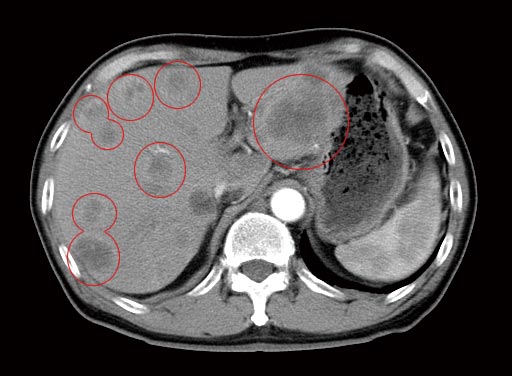

治療前のCT検査結果

治療前CTでは、肝臓全域に広がる多数の肝転移病巣が認められました。